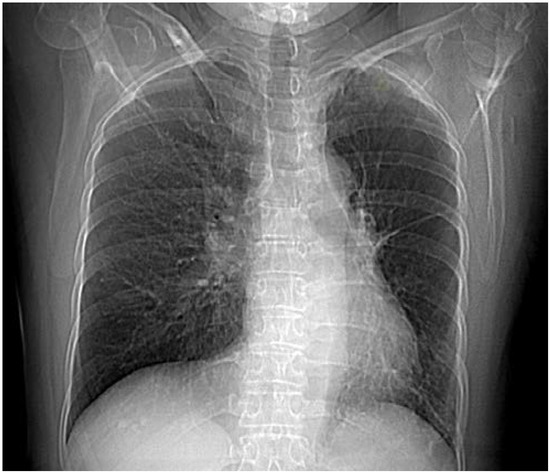

Thorax computed tomography (CT) revealed asymmetry with significantly smaller left lung. The left pulmonary artery immediately after separation was of extremely narrower lumen and so were lobar and segmental branches (Figure 2). Collaterals stemmed from mammary artery and bronchial artery (Figure 3). The results pointed towards UAPA. Subpleurally on the left, apically and basolaterally, scarred changes were noticed.

Figure 2. Computed tomography (CT) showing rudimentary left pulmonary artery.